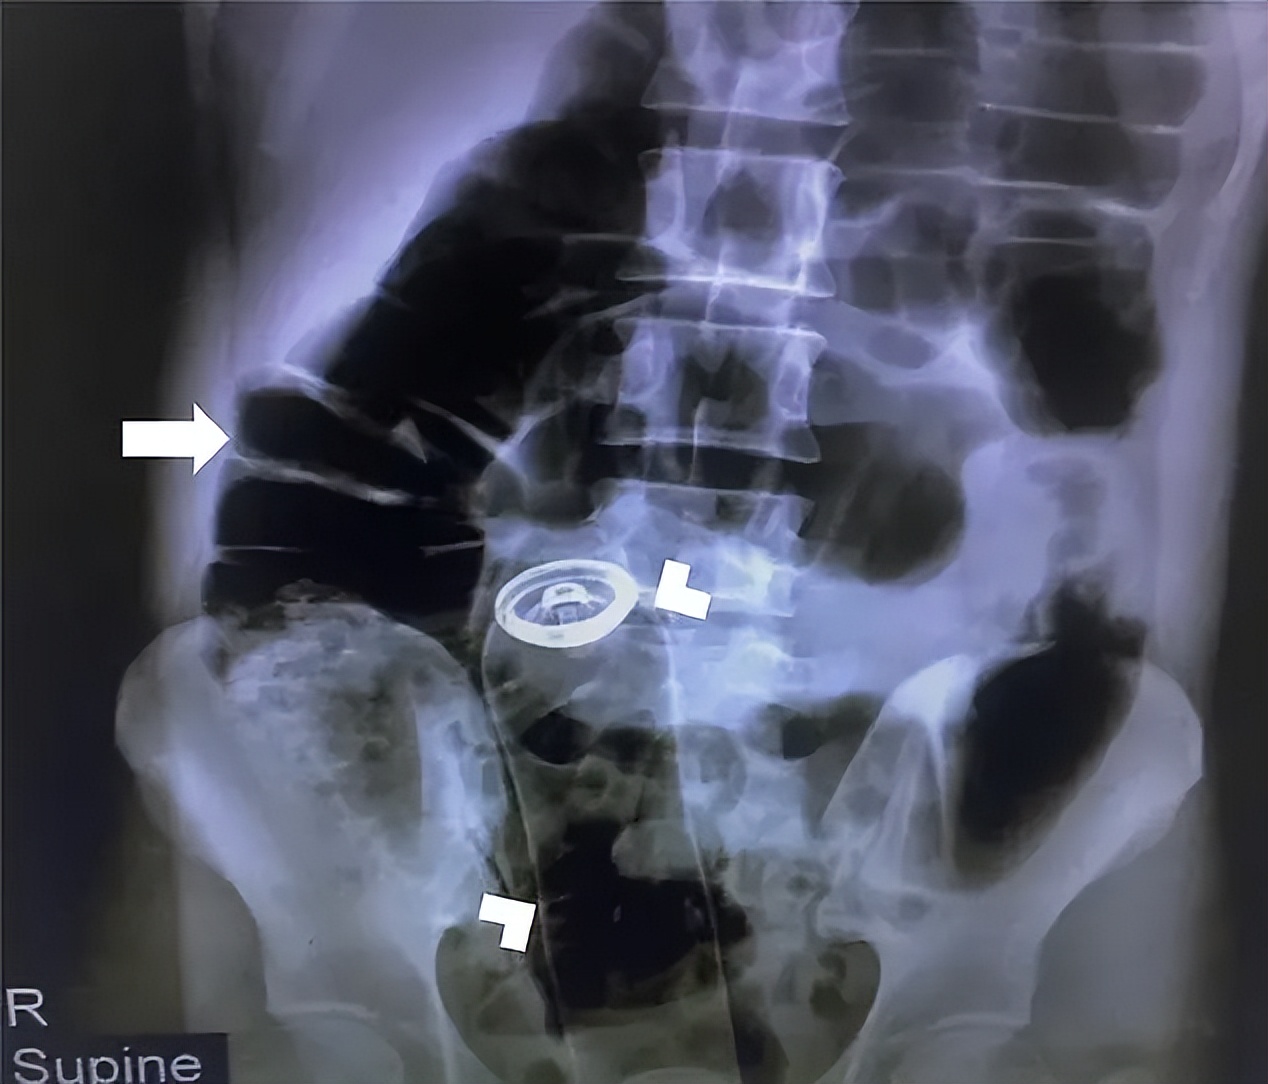

面对这些一问三不知的病人,医生就要给他们做一个全方位的检查,用X光片来帮助他们回忆起病史。这样一来,接诊时间就会被延长,会导致已经有内出血或肠梗阻的患者面临更大风险。

在这份白皮书里就有一个类似病例。这名伊朗病人当时送到急救科时并未主动告知“菊花”被卡,只说自己腹部异常疼痛。

做完X光片后,医生惊讶地发现他直肠里有一大瓶除臭剂,而且异物因为患者的不断收缩,已经跑到消化道了。